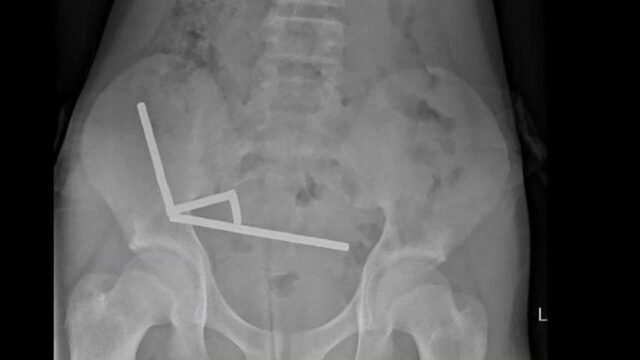

Los escáneres revelaron que los imanes estaban agrupados en cuatro cadenas en la parte inferior derecha de su abdomen, eliminando diferentes partes de su intestino junto con su fuerza magnética, dice el informe, señalando que algunas imágenes fueron distorsionadas por los imanes. Luego los médicos procedieron con una cirugía exploratoria.

Durante el tratamiento, los cirujanos descubrieron que las cadenas magnéticas provocaban necrosis por presión (la muerte del tejido de presión largo) en partes del intestino y del intestino grueso. Consiguieron quitar los imanes, pero el niño tuvo que aspirar parte de su intestino. Pasó ocho días recuperándose en el hospital antes de ser dado de alta, según el informe.